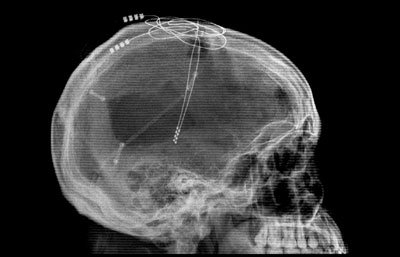

- Better overall behavioural outcomes were noted with bilateral subthalamic deep brain stimulation plus medical therapy vs medical therapy alone for Parkinson’s with early motor complications (EARLYSTIM trial – an open-label randomised trial – Click here to read more).

- In other deep brain stimulation research, researchers found evidence of beneficial effects of bilateral subthalamic nucleus deep brain stimulation on non-motor features of Parkinson’s at 24-month follow-up (Click here to learn more).

Deep brain stimulation. Source: Spiegel